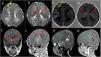

Point-of-care ultrasound of the chest. Linear probe. (A) Transverse plane at the level of the intermammary line. Visualization of sternum (*) and the masses (tubers) in the myocardium (homogeneous, hyperechoic, X). This contrasted with the decreased echogenicity of the myocardium (+). B) Left longitudinal plane: anterior arc of ribs (*), tubers (X), mediastinum (+). gr1.

We present the case of a term newborn infant that underwent a bedside ultrasound examination of the chest due to respiratory distress. Transverse-plane scanning with a linear probe can be used to rule out pneumothorax,2 and in this patient it revealed several well-demarcated hyperechoic lesions up to 2 cm in diameter confined to the myocardium (Fig. 1, Appendix B, supplemental material). The lung parenchyma presented an interstitial pattern in a gradient with a thin pleural line and lung sliding, compatible with transient tachypnoea (respiratory support for 48 h). The echocardiogram confirmed the presence of cardiac tubers, and a brain magnetic resonance evidenced subependymal tubers and nodules (major criteria), radial migration lines, subependymal nodules and cysts in the white matter (Fig. 2) which, combined with the results of genetic testing, led to the diagnosis of tuberous sclerosis type 2 (Bourneville syndrome, pathogenic TSC2 gene variant).